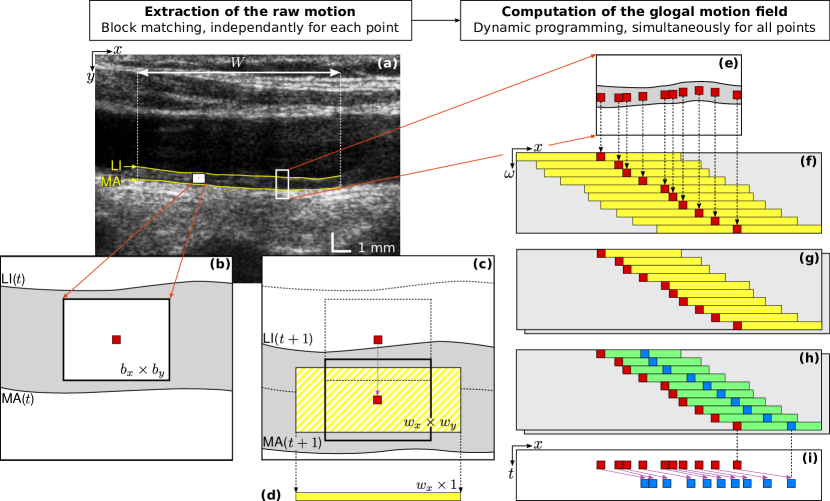

First, a ROI is determined by manually indicating the left and right borders of the full exploitable width of the far wall in order to clip out noisy regions (Figure 3a). All the subsequent steps of the framework are fully-automatic.

In each frame of the image cine-loop, the contours of the lumen-intima (LI) and media-adventitia (MA) interfaces are segmented within the ROI (Figure 3a), using a previously validated method zahnd2017fully . Briefly, the contour segmentation framework is based on a front propagation approach specifically devised to simultaneously (as opposed to one after the other) extract the two anatomical interfaces of the intima-media complex. This is achieved by building a 3D space (LI depth MA depth width), where the minimum-cost path is a medial axis that describes, in each column of the image, i) the center of the intima-media complex, and ii) its thickness. The LI and MA contours can immediately be deduced from the medial axis.

In preparation for a block matching scheme, the contour information is used to populate a mesh of points , with and , in the first frame of the cine-loop. One point is placed in each column of the ROI, in the center of the intima-media complex (Figure 3b,e).

II.2.2 Extraction of the raw motion

This operation consists in estimating the motion field , namely the relative -wise displacement of each point in each frame of the cine-loop. This process being carried out independently for each point, the description of the operation will be given for a single point at a given time step. The previously described interpolation scheme is applied to the frames and . A block matching operation is then carried out between these two consecutive frames: a rectangular block of size is centered around in the frame, and a search window of size is explored in the frame. Matching similarity is evaluated with the sum of squared differences (SSD) metric.

Let us briefly recall three specificities that are most generally followed by traditional block matching approaches: i) the next position of the tracked point is blindly determined by the coordinates of the global minimum in the SSD map, ii) the search window in the frame is centered around , and iii) the reference block corresponds to the speckle pattern centered around the currently tracked point . In comparison with traditional implementations, these three specific points are addressed differently by the present framework, as described hereafter.

First, the search is guided along the direction using a previously validated contour segmentation method zahnd2017fully . The rationale is to perform a first estimate of the wall radial displacement to guide motion tracking and systematically ensure that the tracked points remain within the intima-media complex. Guidance is realized by automatically setting the coordinate of the center of the search window in the center of the intima-media complex in the frame (Figure 3c). The segmentation method has been reported to delineate the LI and MA interfaces with a mean absolute error () of and , respectively zahnd2017fully . Therefore, block matching is conducted along the direction with a reduced maximum displacement , in order to allow a fine search around the initial position provided by contour segmentation. In contrast, since no a priori guidance is provided along the direction, a wider exploration range is permitted, with . This value has been selected based on the maximum expected displacement between two time steps and validated in a previous study zahnd2013evaluation . Given a pixel size of and an interpolation factor of in the longitudinal and radial directions, respectively, the size of the search window in pixels is equal to .

Second, the reference block used within the block matching operation is systematically updated to follow the gray-level variations of the moving images over time, while still preserving the appearance of the initial tracked pattern. The motivation of this implementation is to avoid a potential and irreversible divergence of the trajectory that may be caused by the accumulation of tracking errors due to artifacts and speckle decorrelation. This is accomplished by using a control signal , corresponding to the initial image pattern in the first frame of the cine-loop, to systematically keep the memory of the initially tracked point. To cope with small gray-level variations, the reference block is thus generated by a weighted sum of the current speckle pattern and the control signal , according to the following relation:

| (1) |

Here, is a weighting factor that determines the relative influence of the initial and current speckle patterns in generating the reference block.

Third, the optimal position of the ensemble of all blocks is determined simultaneously by means of a dynamic programming scheme. Please note that the aim of this paragraph is to describe the operations undertaken to prepare the dynamic programming scheme, whereas the dynamic programming algorithm per se is described thereafter in Section II.2.3. For a given tracked point , as part of the block matching operation, a search window is explored, resulting in a 2D SSD map of size (Figure 3c). From this map, a 1D similarity vector of length is generated by selecting the smallest value in each column of the initial 2D SSD map (Figure 3d). Therefore, at this stage, no decision is taken regarding determining the displacement of any single point: instead of selecting the candidate point with the lowest value in the 2D SSD map, the matching potential along the direction is stored for further use. The rationale is to simultaneously determine the optimal -wise displacement of the ensemble of all blocks by using the collection of similarity vectors in a dynamic programming scheme, as described in the following paragraph. Let us also remember that the displacement along the axis has already been determined by the contour segmentation.

II.2.3 Computation of the motion field

In this step, at a given time , the ensemble of 1D similarity vectors , resulting from the raw motion estimation of the points , are considered collectively. A combinatorial analysis is performed to determine, among all possible solutions describing the displacement of the ensemble of all points, the optimal motion field given the following rules: i) data similarity: displacement is guided by the SSD matching criterion represented by the 1D similarity vectors , ii) non-crossing trajectories: the initial ordering of the points along the axis does not change, iii) motion smoothness: increase or decrease of the -wise distance between two neighboring points is penalized, and iv) motion uniformity: between two successive frames, all moving points must either follow a displacement towards the right or left side of the image. The implementation enforcing these rules is described below.

A dynamic programming algorithm based on front propagation is proposed. A cost function is constructed in the artificial space , where each 1D similarity vector is oriented along the direction and centered on (Figure 3f). Here, the axis of the coordinate system corresponds to the left-to-right ranking of the points: two neighbors points and yield . The values of outside of the region covered by the maps correspond to non-reachable positions, and are therefore set to infinity.

The condition of motion uniformity is addressed by using to generate two cost functions (Figure 3g). In each row of (respectively, ), the value of the points whose -coordinates are strictly smaller (respectively, larger) than is set to infinity, thus enforcing a global displacement to the right (respectively, left).

A front propagation is then run to build two cumulative cost functions and . For , is initialized with the corresponding values of . Then, for , is iteratively generated according to Equation 2.

| (2) |

To provide a more intuitive grasp of this relation, the cumulated cost of the current node (first line, left part) is determined as the minimal value, across a reachable neighborhood , of the addition of i) the cumulated cost of the previous node (first line, right part), and ii) the sum of the cost of the current and previous nodes (second line) multiplied by a factor to penalize non-realistic distances between the two nodes (third line). Here, prevents crossing point trajectories, namely to respect the condition given two points and such that . The elasticity of the mesh is controlled by the smoothing coefficients , , and , as well as by the parameter , which represents the expected -wise distance between two adjacent points, namely one pixel in the original image corresponding to ten pixels in the interpolated image. The distance penalty is null when two neighbors points are separated by exactly ten pixels (one pixel in the non-interpolated image), and gradually becomes greater when the distance between these two points increases (stretching) or decreases (compression). A schematic representation of the front propagation is provided in Figure 4.

Finally, the optimal paths and are extracted in both and via back-tracking zahnd2017fully from the point having the minimal cumulated cost (Figure 3h). The solution with the minimal cost among and is used to determine the motion field such that (Figure 3i).